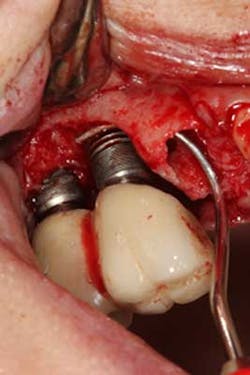

There have been numerous case reports in the literature demonstrating infections of dental implants caused by pathology from the adjacent natural tooth. (1) These infections from adjacent teeth can travel quite quickly to the proximal dental implant (figures 1a and 1b) and cause a rapid degree of bone loss. Treatment can consist of loss of teeth, loss of the dental implants, and/or costly regenerative repair (figure 2). (2) This situation is highly preventable if detected early and endodontic therapy is initiated.